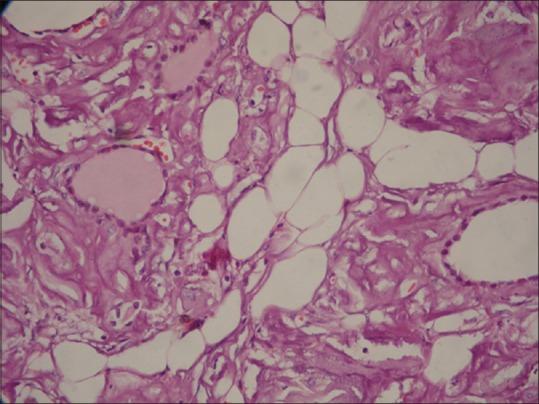

The association between amyloidosis and collagen vascular diseases, such as rheumatoid arthritis (RA) is well-documented. Amyloid goiter is an extremely rare pathologic condition caused by a massive amyloid infiltration of the thyroid tissue. Our patient had been diagnosed with RA 20 years ago and was on hemodialysis for 7 years. He was assessed for decreased appetite, dysphagia, and nausea during the hemodialysis. On physical examination, the thyroid was diffusely enlarged with multiple nodules. He was biochemically euthyroid. Ultrasound of the thyroid gland showed multinodular goiter. A total thyroidectomy was performed. Histopathological examination showed dilated follicles surrounded by abundant homogeneous substance that stained positive with Congo red. The patient was reported as amyloid goiter. Complaints of the patient improved after the surgery. In the literature, amyloid goiter with RA in a hemodialysis patient is very rare. Amyloid goiter should be considered if there is a rapid thyromegaly causing pressure symptoms in the background of any disease with chronic inflammation.

淀粉样变性与胶原血管疾病(如类风湿关节炎(RA))之间的关联已有充分记录。淀粉样甲状腺肿是一种极为罕见的病理状况,由甲状腺组织的大量淀粉样蛋白浸润所致。我们的患者20年前被诊断为RA,已接受7年血液透析。在血液透析期间,对其进行了食欲减退、吞咽困难和恶心的评估。体格检查发现甲状腺弥漫性肿大,有多个结节。生化检查显示甲状腺功能正常。甲状腺超声显示为结节性甲状腺肿。遂行甲状腺全切除术。组织病理学检查显示滤泡扩张,周围有大量均匀物质,刚果红染色呈阳性。该患者被诊断为淀粉样甲状腺肿。术后患者的症状有所改善。在文献中,血液透析患者合并RA的淀粉样甲状腺肿非常罕见。在任何伴有慢性炎症的疾病背景下,如果出现导致压迫症状的快速甲状腺肿大,应考虑淀粉样甲状腺肿。